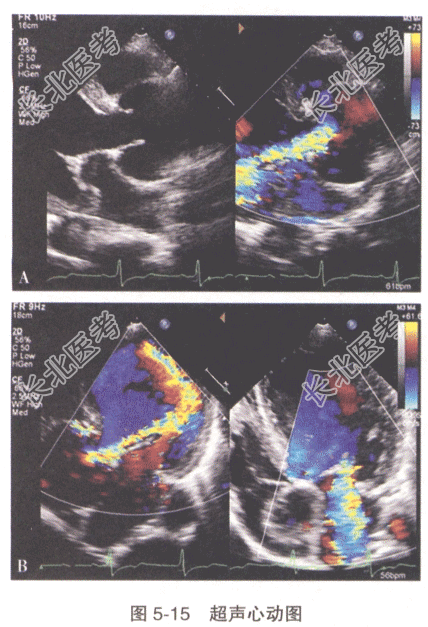

患者,男性,28岁。因“胸闷、心悸多年,近1个月自觉症状加重伴气促”入院,查体:患者瘦高体型,四肢细长,漏斗胸,蜘蛛痣,生命体征平稳。心脏彩超检查见图5-15:主动脉窦部瘤样扩张,升主动脉及主动脉弓部增宽(A图)。主动脉瓣瓣叶稍厚,回声稍强,开放幅度尚可,舒张期可见偏心性反流信号沿二尖瓣前叶走行(B图)。